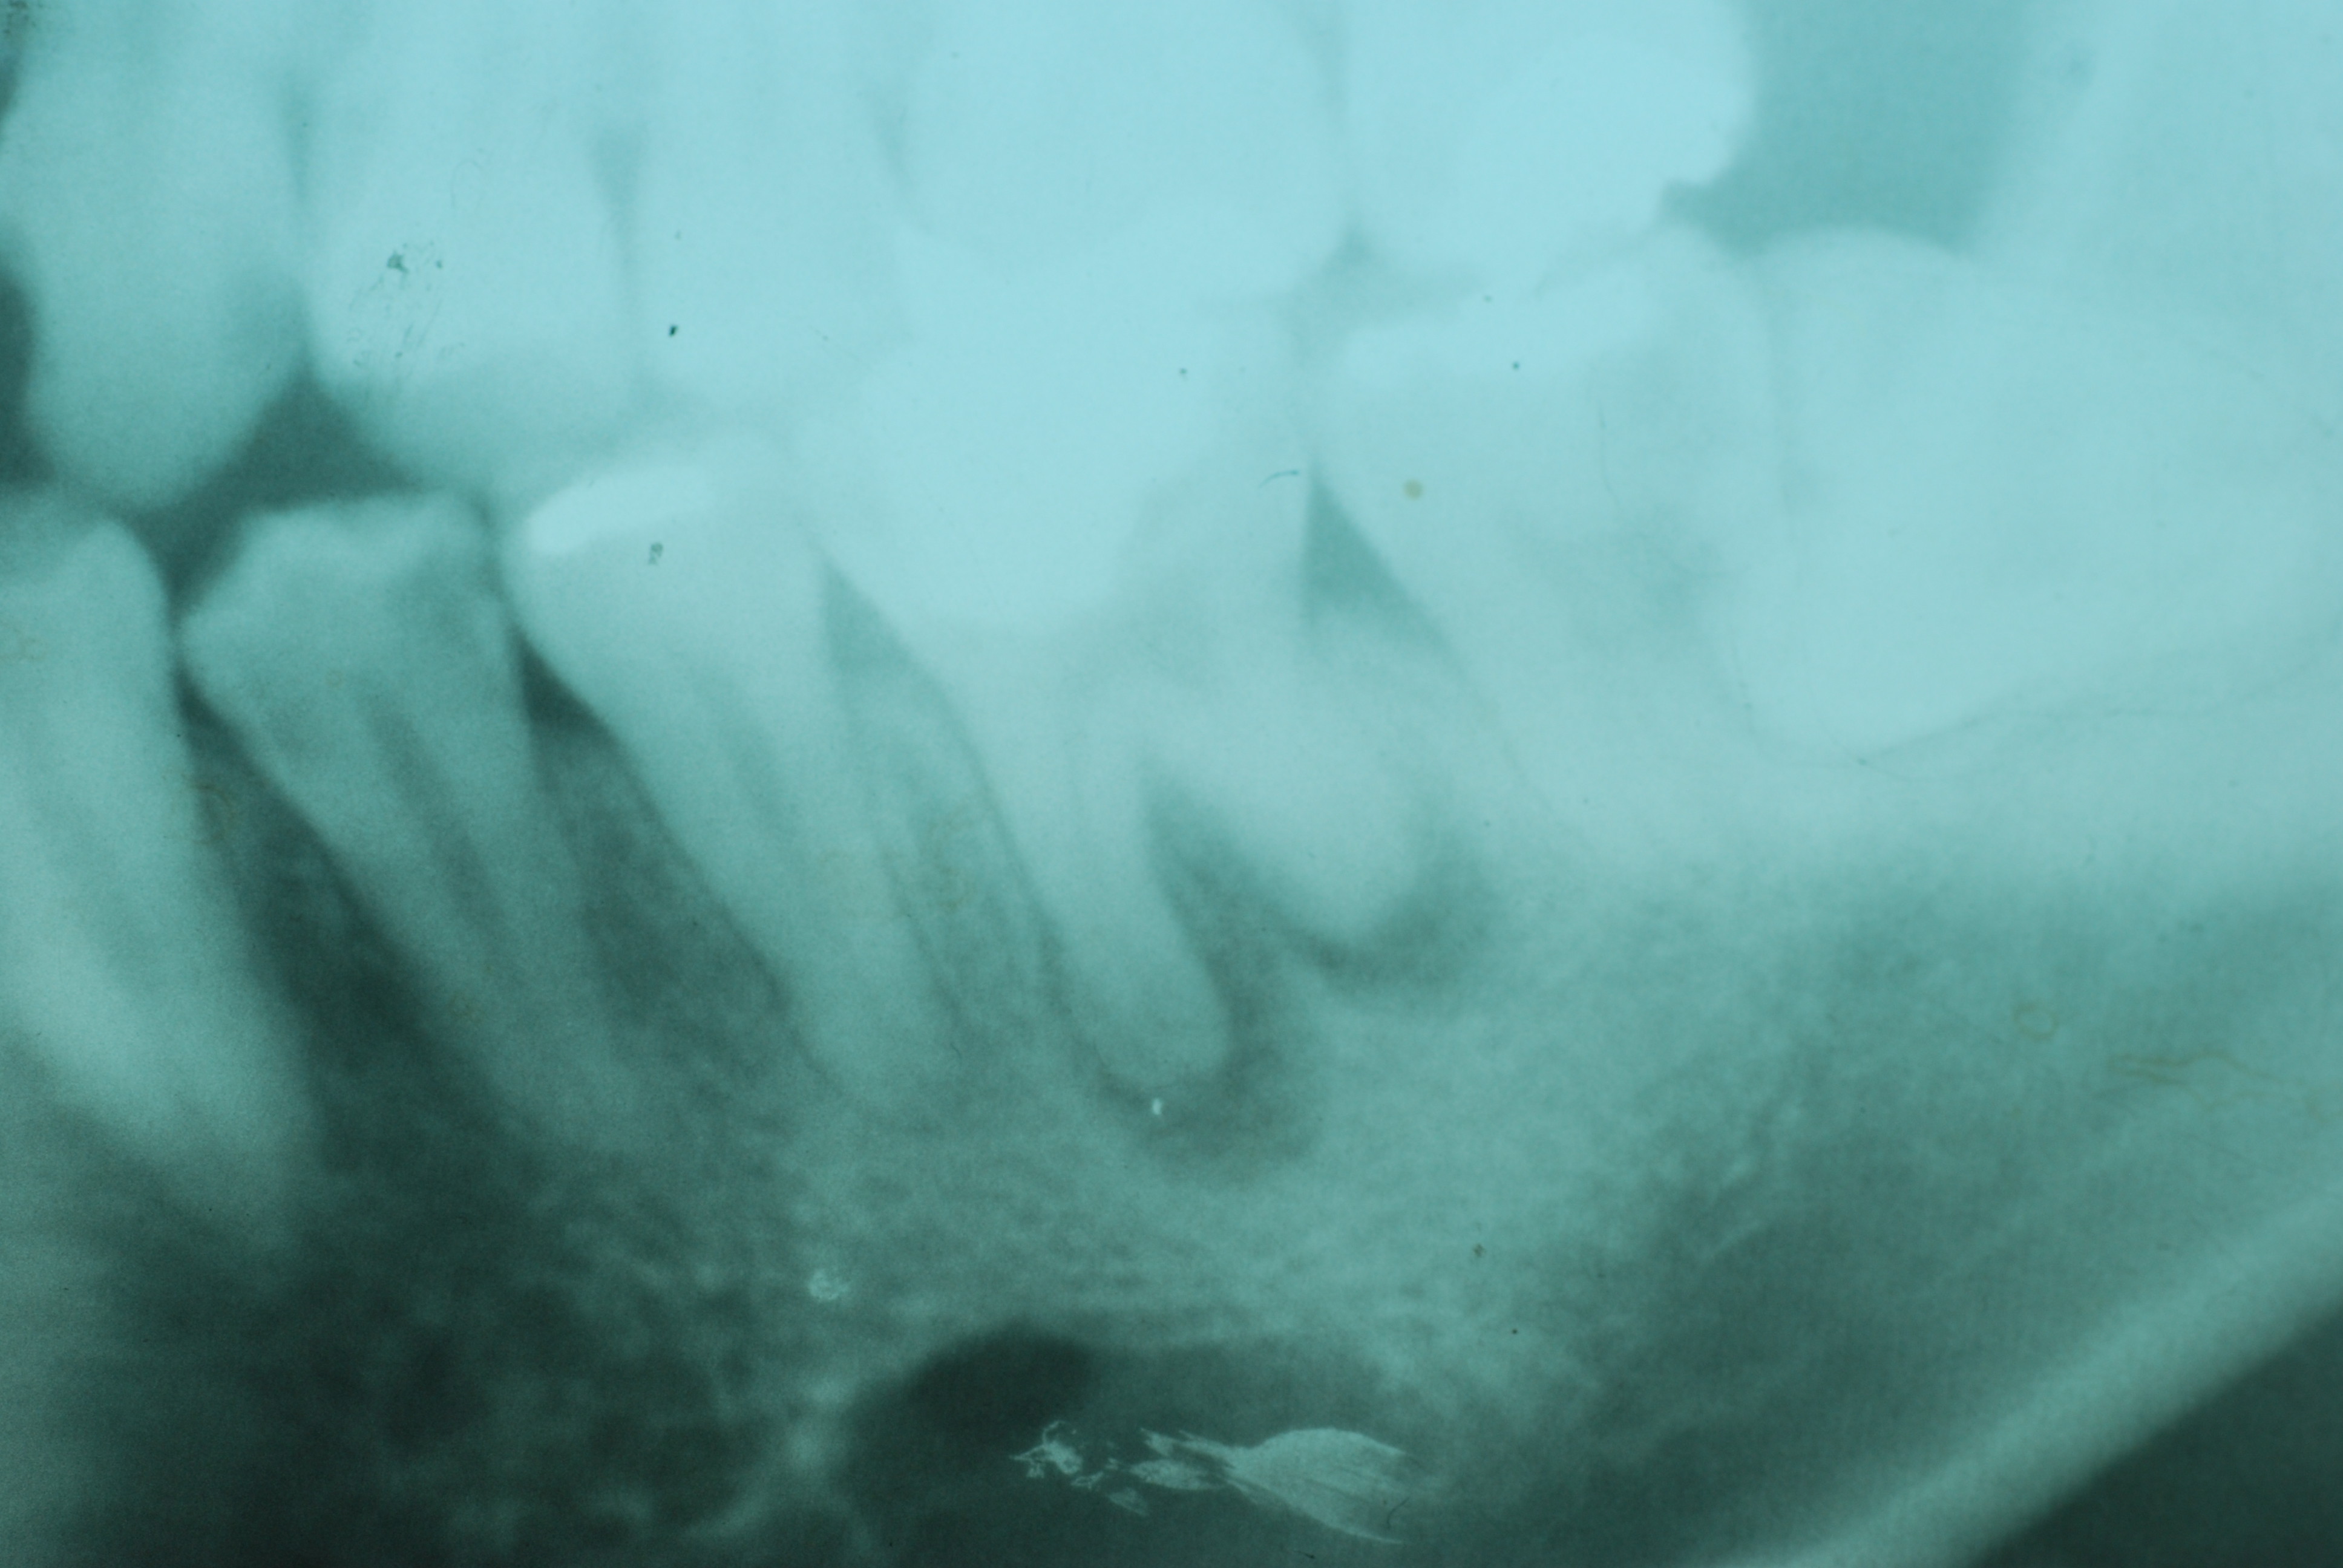

必ずばい菌が侵入しないようにしてばい菌である虫歯を除去します。

銀歯の下はばい菌だらけです。こういうのはよくあります。取り残しですね。![treatment_05[1]](https://livedoor.blogimg.jp/netdental/imgs/3/a/3ad019d0-s.jpg)